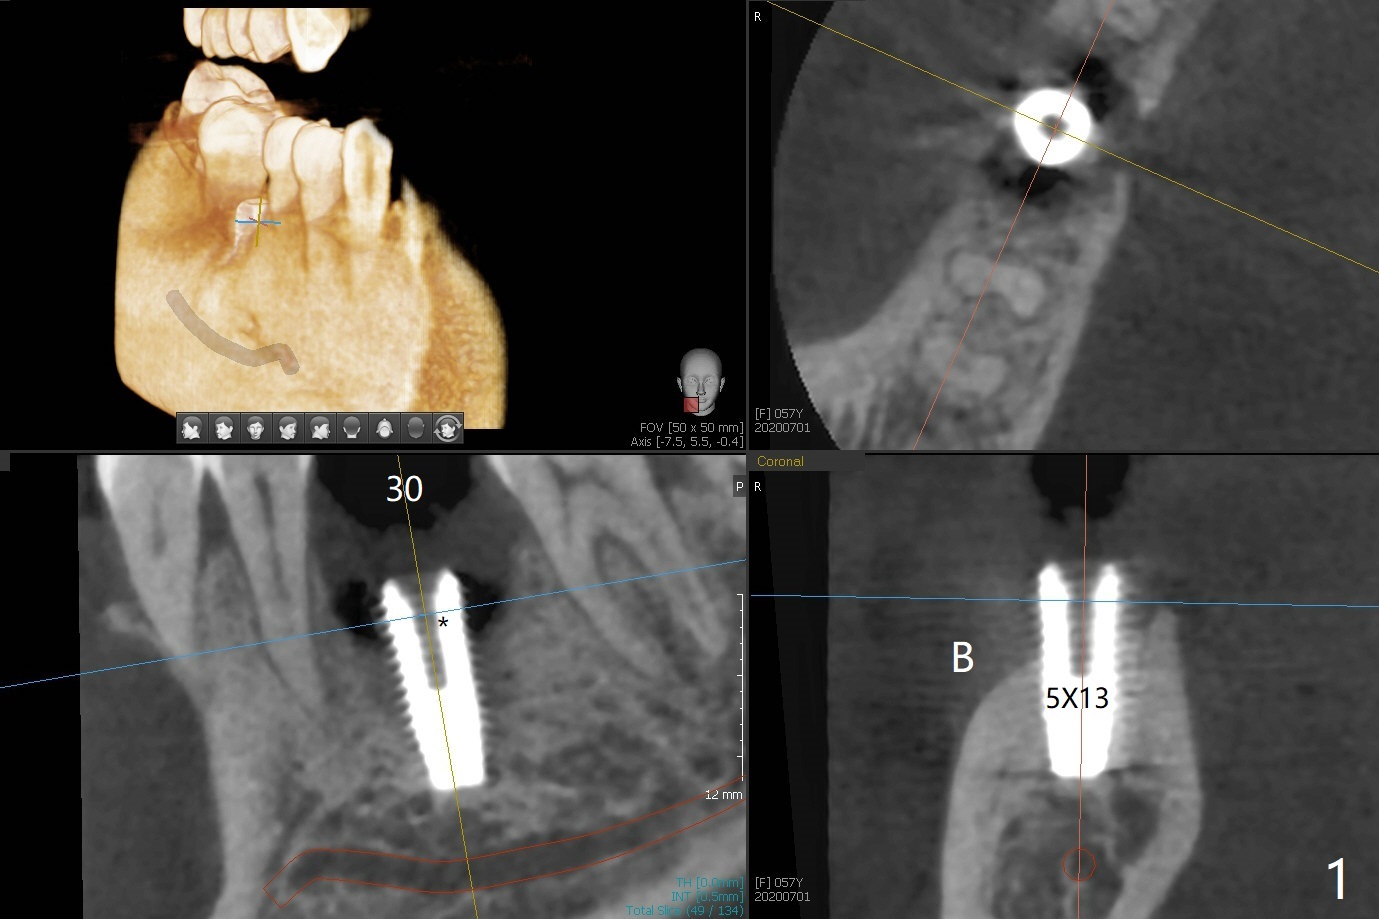

When the woman with periimplantitis at #30 returns to clinic, the abutment is found to be fractured (Fig.1 *) and difficult to remove. After implant removal with trephine burs, osteotomy is initiated lingual (Fig.2). A smaller and shorter implant (4.5x11.5 vs. 5.0x13 mm previously) is placed deeper (Fig.3) so that there is space for sticky bone buccal and coronal (Fig.4 *, 5 (postop reanalysis of preop CT)). After placement of 2 pieces of PRF membranes, the wound is closed with 4/0 PGA. The buccal flap is perforated due to periimplantitis and surgical manipulation. Periodontal dressing is applied.